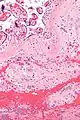

| Micrograph of a chronic deciduitis, showing the characteristic plasma cells. H&E stain. | |

It is associated with preterm labour.[1] The diagnosis rests primarily on the presence of plasma cells.[2]